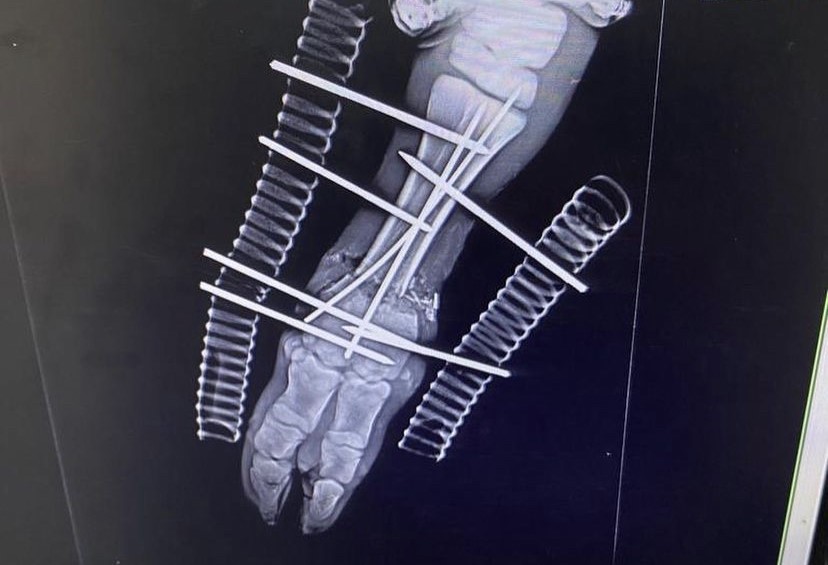

Zonguldak’ın Çaycuma İlçesinde Dereköseler köyünden doğum esnasında buzağının kırılan ön bacağına 6 platin takıldı.

Edinilen bilgiye göre olay Çaycuma İlçesi Dereköseler köyünde meydana geldi. İddiaya göre bir ineği doğum esnasında buzağının ön bacağı kırıldı. Hayvan sahiplerinin fark etmesi üzerine hemen kent merkezinde veteriner kliniğine getirildi. Veteriner hekim Önder Alkan tarafından muayene edilen buzağı hemen ameliyata alındı. Buzağının kırılan ön ayağına 6 platin takıldı. Ameliyat sonrasında veterinerden taburcu edilen buzağının yürümeye başladığı öğrenildi.